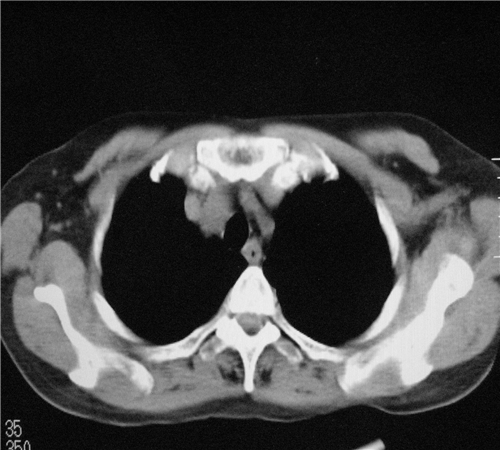

标题: CT26849:女67岁反复胸痛两天余,临床考虑夹层。 [打印本页]

标题: CT26849:女67岁反复胸痛两天余,临床考虑夹层。

右肺感染,未见夹层。

既然考虑夹层,建议强化!另:右下肺感染!

1)右肺感染性病变。2)建议行ct增强扫描或mri检查排除主动脉夹层。

双下肺感染,右侧显著。有无夹层,增强扫描后再诊断。

1. 感染性病变,2.未见夹层,3.食道未见异常。

1.考虑双肺感染,右侧为重;2.建议ct增强或mri排除主动脉夹层

平扫未见确切夹层征,建议必要时增强扫描或mri检查。